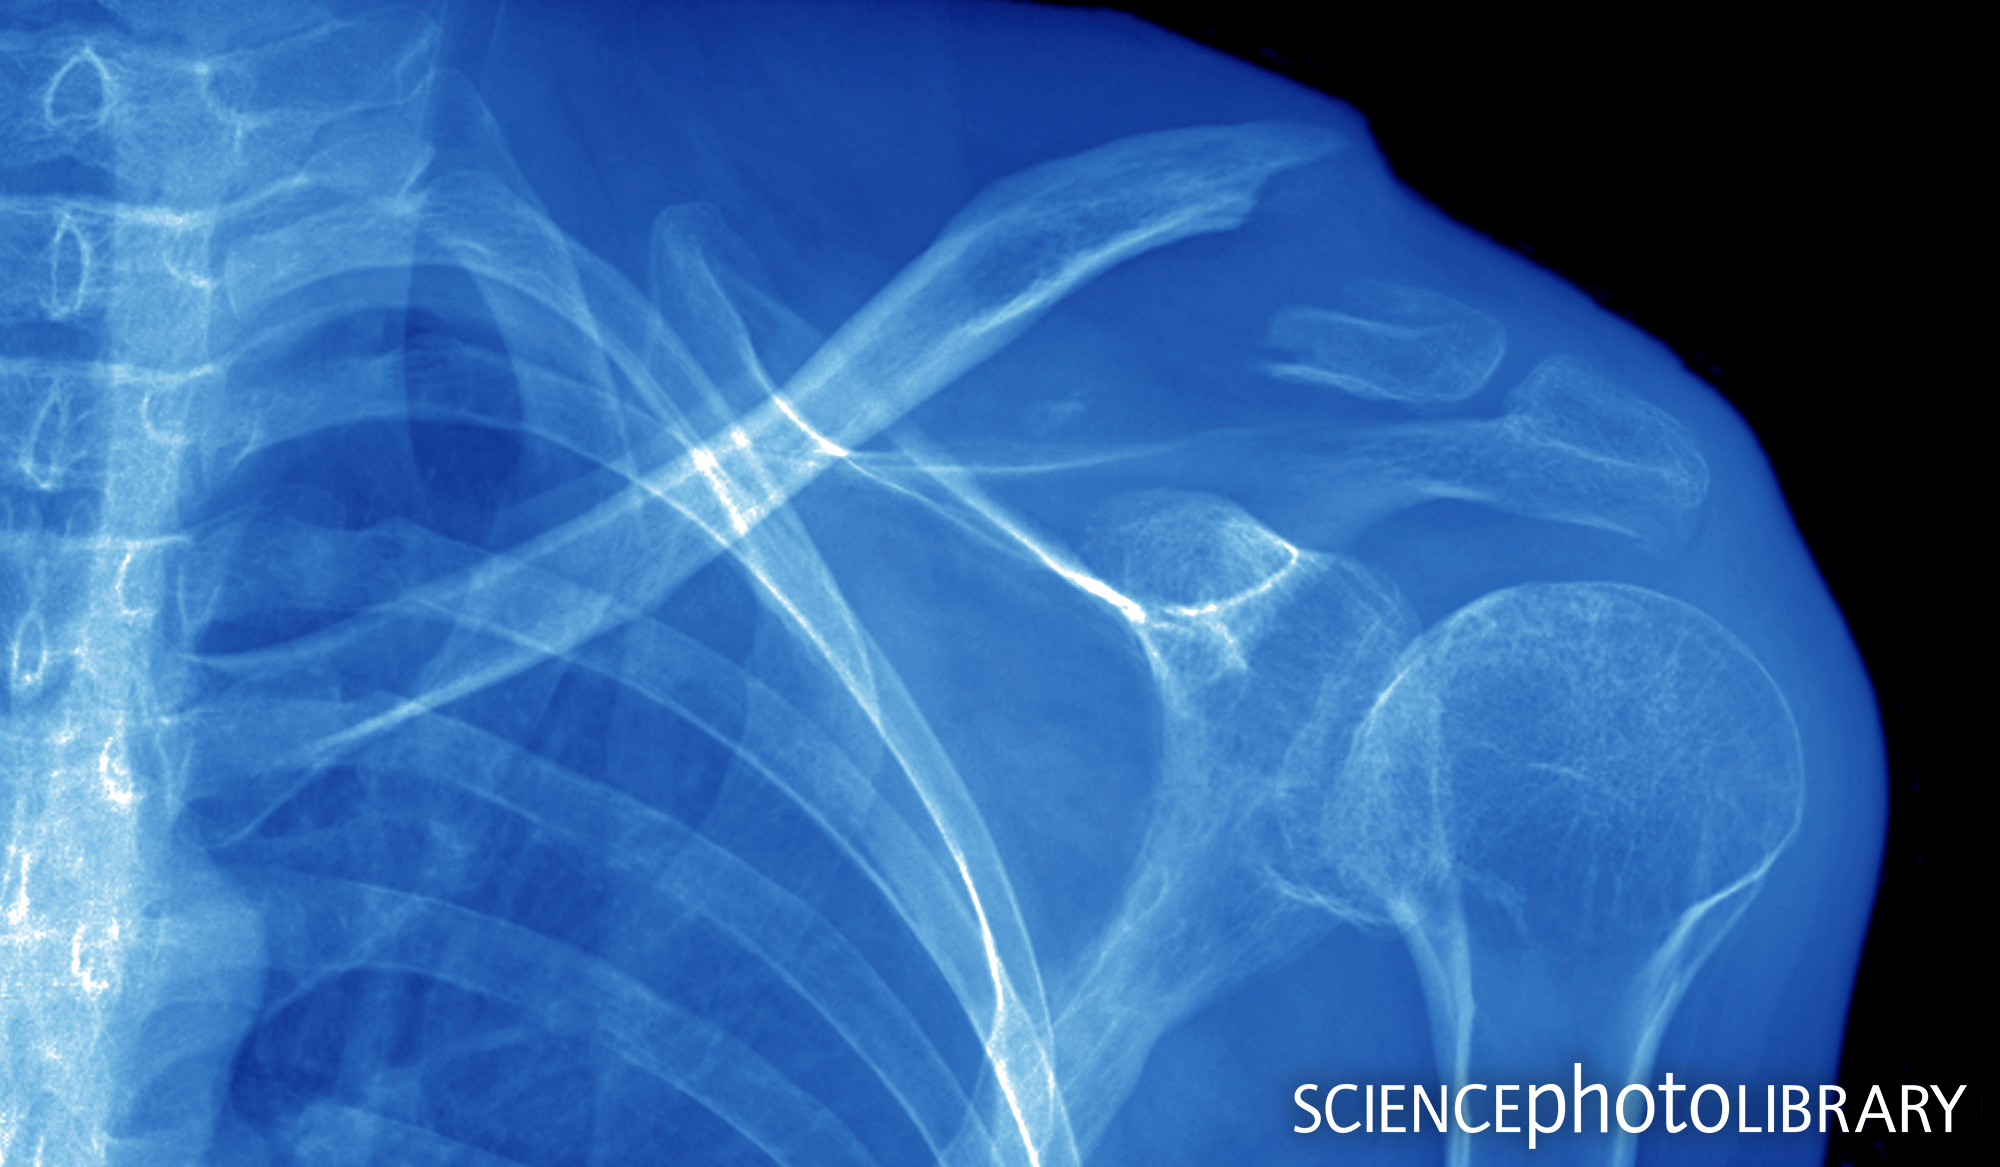

X ray broken collar bone. Broken Collarbone: Symptoms, Causes, and Clinical Management

What radiological investigations should be ordered for a suspected clavicle fracture? X-rays are the primary diagnostic tool and should be obtained to assess the fracture location and characteristics. Anteroposterior and 45-degree cephalic tilt views are typically required to fully visualize the clavicle.

Standard anteroposterior (AP) and AP with 15 degrees cephalic tilt x-ray of the clavicle will show the fracture in two planes and define displacement.

CT Scan is very seldom required. It may be needed in medial third injuries to assess tracheal impingement and thoracic anatomy, or in displaced lateral third injuries to assess the coraco-clavicular ligament, with orthopaedic consultation.![]()

6. What do they look like on x-ray?

Middle third fracture

Seven year old boy with angulated (not translated) fracture of the middle third of the clavicle.

A middle third fracture with greater than 100% displacement

Lateral third

Figure 2: Undisplaced lateral third fracture of the clavicle in a 12 year old boy.

Sternoclavicular dislocation (posterior displaced)

Figure 3: A) 14 year old with posterior dislocation of the medial end of right clavicle.

This is difficult to see on x-ray. B) The posterior dislocation (red arrow) is more evident on CT scan.